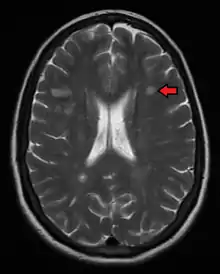

Multiple sclerosis as seen on MRI

Magnetic resonance imaging (MRI) of the brain and spine may show areas of demyelination (lesions or plaques). Gadolinium can be administered intravenously as a contrast agent to highlight active plaques, and by elimination, demonstrate the existence of historical lesions not associated with symptoms at the moment of the evaluation.[82][83]